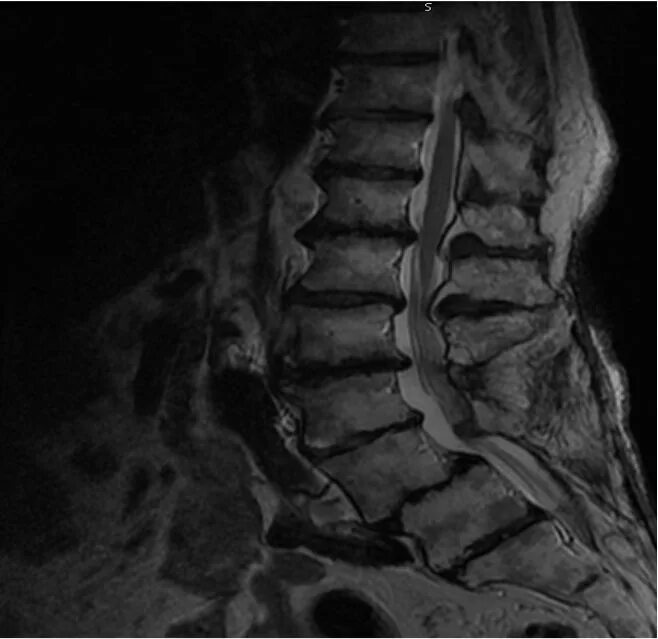

Spine mri